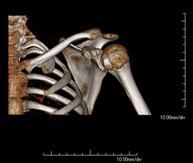

- TC Hombro

Exploración radiológica que mediante un sistema de rayos X y detectores que giran alrededor del paciente, reconstruyendo las imágenes por ordenador (TC Multidetector), permite el estudio de huesos, músculos y articulaciones del hombro. - TC Codo